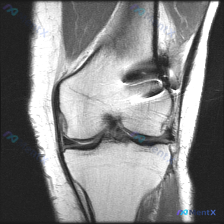

今天整理了一张膝关节MRI的读片分析,这个病例的思路很有代表性,分享给大家。 病例影像基础信息 这是一张膝关节MRI矢状位T1加权像,图像质量良好,对比度清晰,无明显伪影,层面可显示股骨髁、胫骨平台、交叉韧带等核心结构。 系统读片结果 1. 骨与软骨整体情况:股骨远端、胫骨近端骨髓信号均匀,无局灶低...